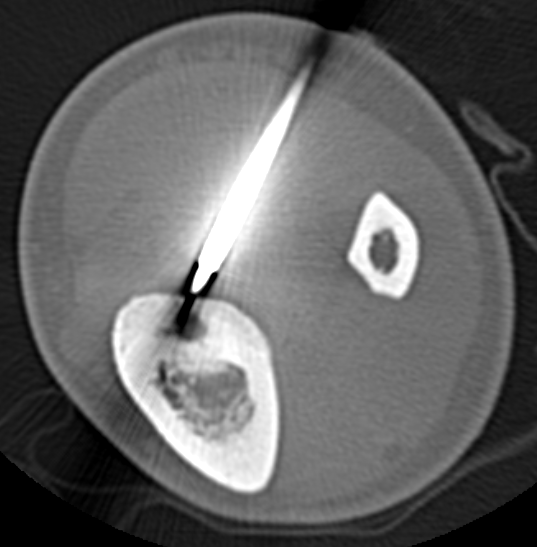

CT

Best investigation

- lucent nidus surrounded by dense bone

Osteoid osteoma tibia

Technique

GA

- introduce electrode under CT

- tissue for histology

- radiofrequency

- increase temperature to 90o for 4 - 6 minutes